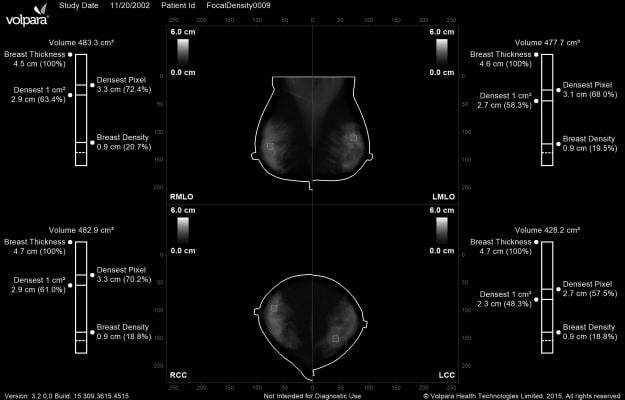

- VolparaDensity helps radiologists assess breast density more objectively and helps them better consider who might benefit from additional screening. The volumetric Volpara Density Grades have been shown to correlate strongly to the sensitivity of mammography and have demonstrated a strong association with the risk of developing breast cancer;